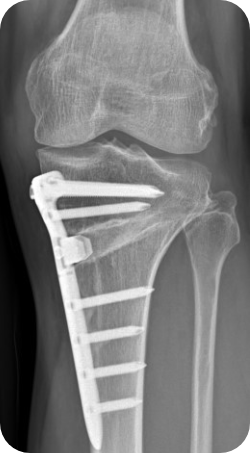

무릎 내측 관절면의 관절염이 심한 경우 관절 간격이 좁아지게 되면서 다리가 O 자형으로 변하게 됩니다. 이런 상태를 방치하게 되면 무릎 내측에 실리는 체중 부하가 늘어나면서 관절 간격이 더 좁아지게 되는 악순환이 이어지게 되는데, 이런 경우 다리의 모양을 1자형 혹은 X자형으로 만들어 무릎 관절 내측에 실리는 체중 부하를 줄이고, 관절염의 진행을 막을 수 있는 수술 방법이 근위경골 교정 절골술 입니다.

- 65세 이하 무릎 내측에 국한된 관절염

- O 다리, X 다리 등 휜 다리인 경우

- 무혈성 괴사나 박리성 연골 파열이 치료에도 호전되지 않는 경우

- 내측 반월판의 후방 부착부 파열이 보존적 치료에도 호전되지 않고 동통이 있는 경우